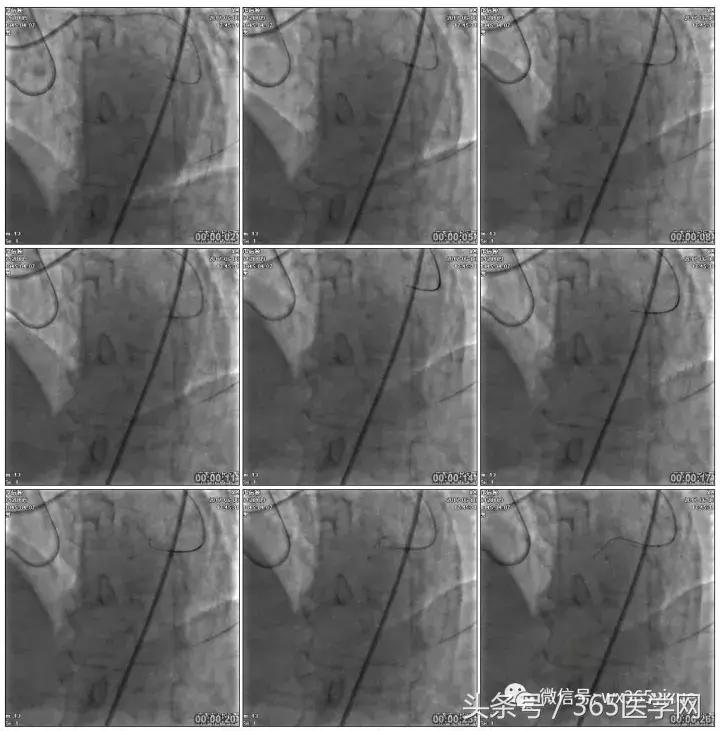

RCA闭塞段球囊扩张后IVUS

支架术后造影结果

支架术后IVUS

小结

-

CTO介入前要认真读图,详细制定介入策略及步骤,

-

明确IVUS在CTO介入的重要性,

-

Guidezilla辅助下的ReverseCART更加高效,

-

Knuckle导丝技术在CTO介入中的使用。